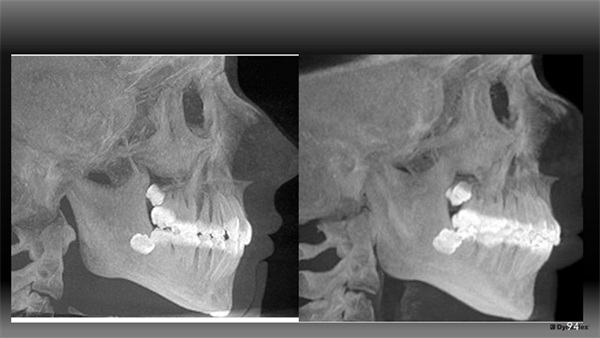

Next, we considered micro/tooth aesthetics and occlusion. If our treatment goal is to advance the A-P position of her upper incisors to benefit her lip position and her upper incisor aesthetic projection within her smile, this demands that the lower incisors will be proclined/rolled forward as well to properly couple with that new forward position of the uppers. When considering changes in lower incisor position, visualizing the mandibular alveolar housing can be valuable. Looking at CBCT images (Fig. 4), she had what I would grade as a thicker type of alveolar housing in the mandibular arch. The possibility of her periodontally tolerating that proclining/rolling forward of her lower incisors was reasonable to me.1

The Architects of the Lips: Part 4

Fig. 4